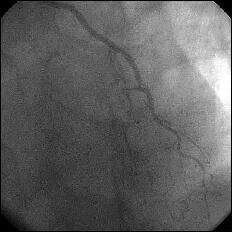

����ALCx take off lesion ��PCI���s���܂����B

�����搶�̌䏕����q�����ċ}篁A�a�i�����搶�j�ɗ���ŗ��Ē����܂����B

CBA(3.5?)+STENT(3.5�~13?)��strategy�ōs������ɂ��Ă��܂������A

�����ő��Z������܂����B

�ƂĂ����p���������̂ł����A�O���ɂق��̐搶��CB(3.5?)���g�p���ꂽ�̂�c��

���Ă��炸�A

�h��������3.5?�o���āI�h�ƌ�������A�h����g�������炠��܂���I�h�Ƃ���

�������Ԃ��Ă��܂����B

��������Stormer(3.5�~15?)��pre������STENT����悤�Ǝv������pre��distal����

�ɑ傫���Ă��܂��A���ǂ����̒ʂ�S670(3.5�~24?)������H�ڂɂȂĂ���

���܂����BCB�������炱��ȂɗȂ����������Ȃ��`�Ƃւ���ł��܂��܂����B

���҂���A�a�A�����Ă��������A�h�o�C�X�����������搶���A�\����܂���B

���x����͑O���ɂ������device�Ƀ`�F�b�N������悤�ɂ��܂��B

�ꉞ�A���ʂ�Y�t���܂��B